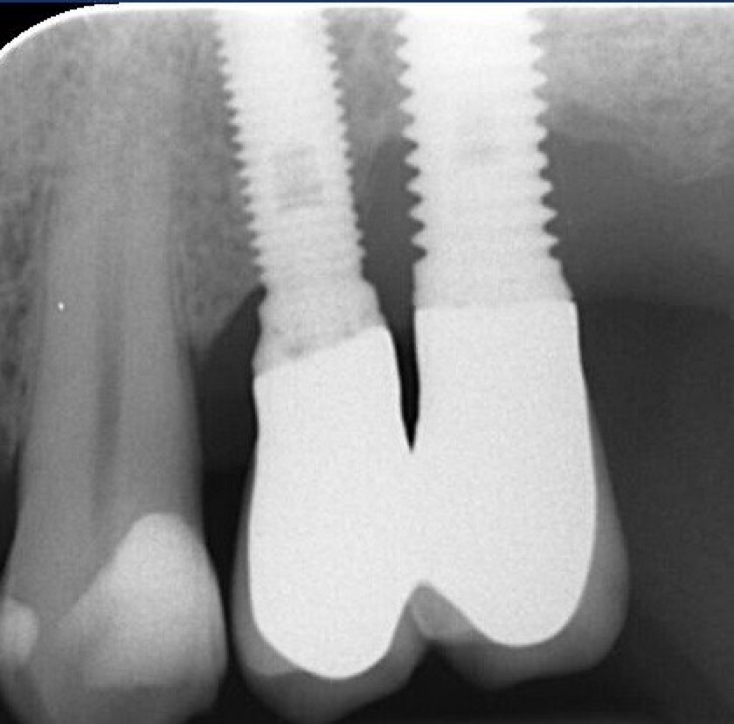

Crestal Bone Loss sets another ambiguous point because an adaptive change of the marginal bone level is known to occur afterimplantplacement and restoration.1It’s necessary to agree a baseline for the radiographic evaluation of bone level changes and set an acceptable bone loss rate. Basing on longitudinal clinical studies, it’s rational to chose the time of prosthesis installation as a reference from which the disease can be diagnosed and followed.14 Basing on Albrektson and Zarb review, 1.5mm of bone loss in the first year and less than 0.2mm annually are considered success criteria.1 A CBL exceeding this rate testifies the risk of implant failure. Don't forget that intra-oral x-rays allow to evaluate the interproximal bone level only, missing an appropriate vision of the buccal/lingual sides, where probing becomes essential. Bleeding on Probing is the key parameter for peri-implant disease diagnosis.13 Presence of BOP can be found in 91% of implants with peri-implantitis and its absence is regarded as a reliable predictive parameter of implant health.12

So far, there is no scientific evidence supporting the efficacy of this coadjuvant. The tested protocol consist of a Multiple Anti Infective Non Surgical Therapy (MAINST) that involves the use topical 14% doxycycline to solve the peri-implantitis acute phase and, after 7 days, a session of Full Mouth Air Polishing Therapy (FM-EPAPT) through erythritol powder (Fig.7), a piezo-ceramic device with a PEEK tip (Fig.8), the curettage of internal pocket line (Fig.9) and a second application od Doxy. The patients were further followed with quarterly maintenance sessions carried on with the same FM-EPAPT protocol. Up to 12 months BOP and mean PD decreased significantly and successfully, accompanied by a gain of attachment level up to 12 months. The first case-series about MAINST is waiting to be published and the results are encouraging. Figure 10 and 11 show the healing at 6 and 12 months after MAINST protocol of the peri-implantitis case displayed at the beginning of this article (Fig.1,2,3,4) and figure 12-21 show a complete MAINST case.